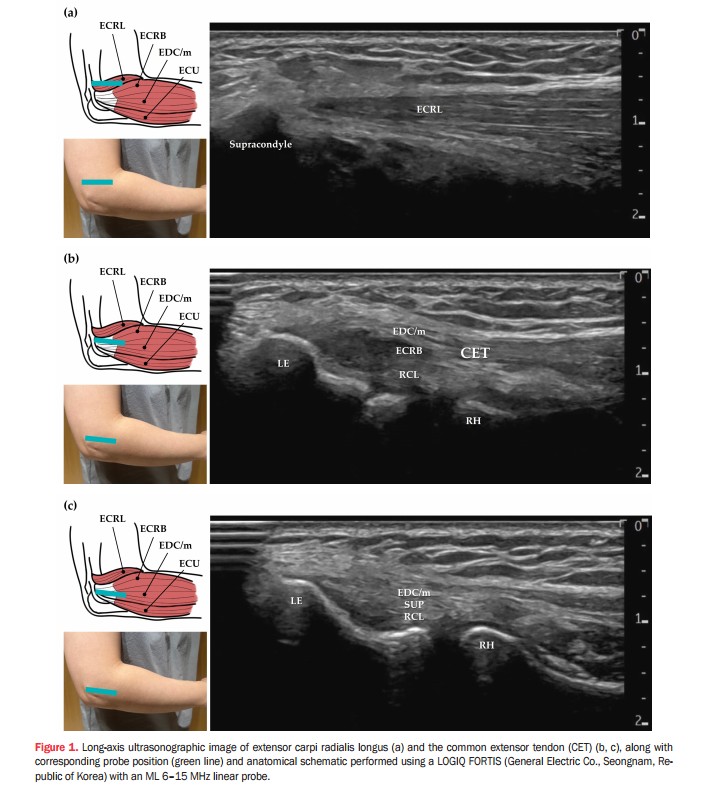

이번 연구에서 안태석 한의영상학회 교육이사(제1저자)는 외측상과염의 주된 원인인 단요측수근신근(ECRB) 병변을 놓치는 경우가 많다는 점에 주목했다. 이를 해결하기 위해 주료(LI12) 혈자리의 ‘상완골 상과’를 해부학적 랜드마크로 삼아 상완골 외상과에 부착하는 공통신전근 힘줄 전체를 체계적으로 평가하는 표준화된 경혈 초음파 프로토콜을 제시했다.